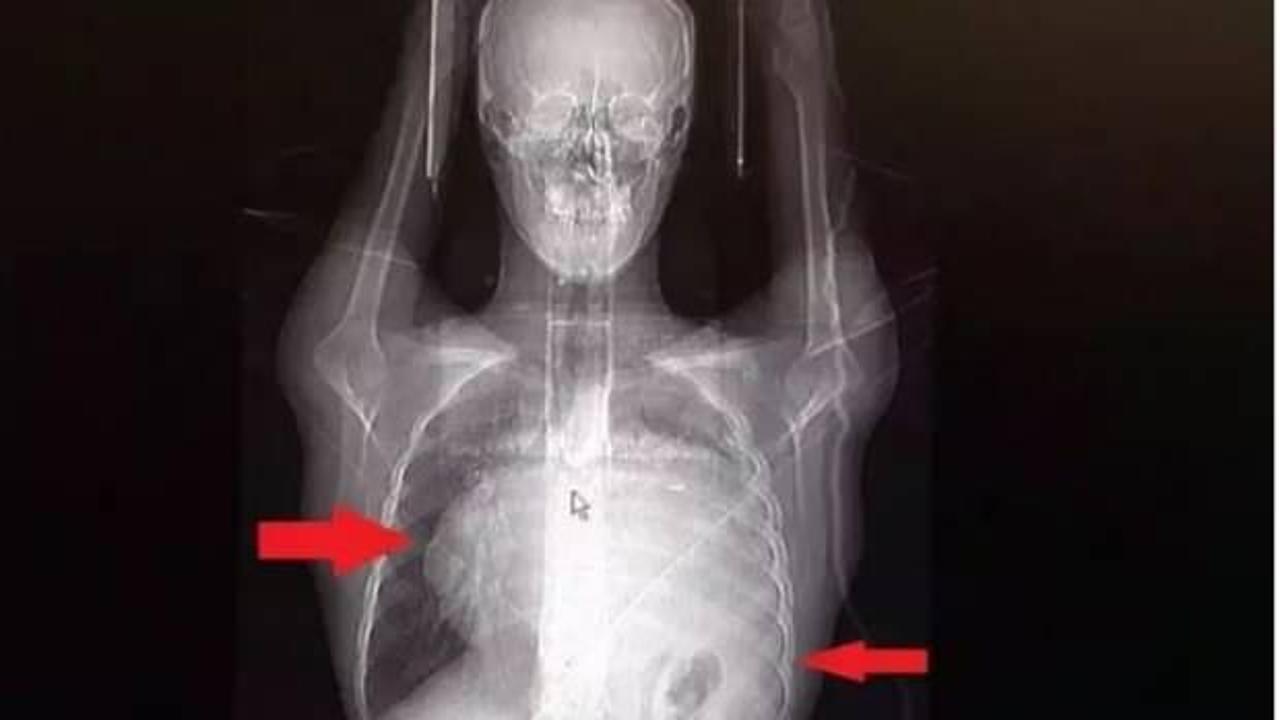

İstanbul'da yaşayan Burak Aktaş (21), Ağustos ayında halsizlik ve nefes darlığı şikayeti ile doktora gitti. Sol göğüs boşluğunda portakal büyüklüğünde bir kitle tespit edildi.